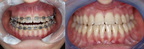

Korekcija deformiteta kostiju lica: Otvoreni zagriz